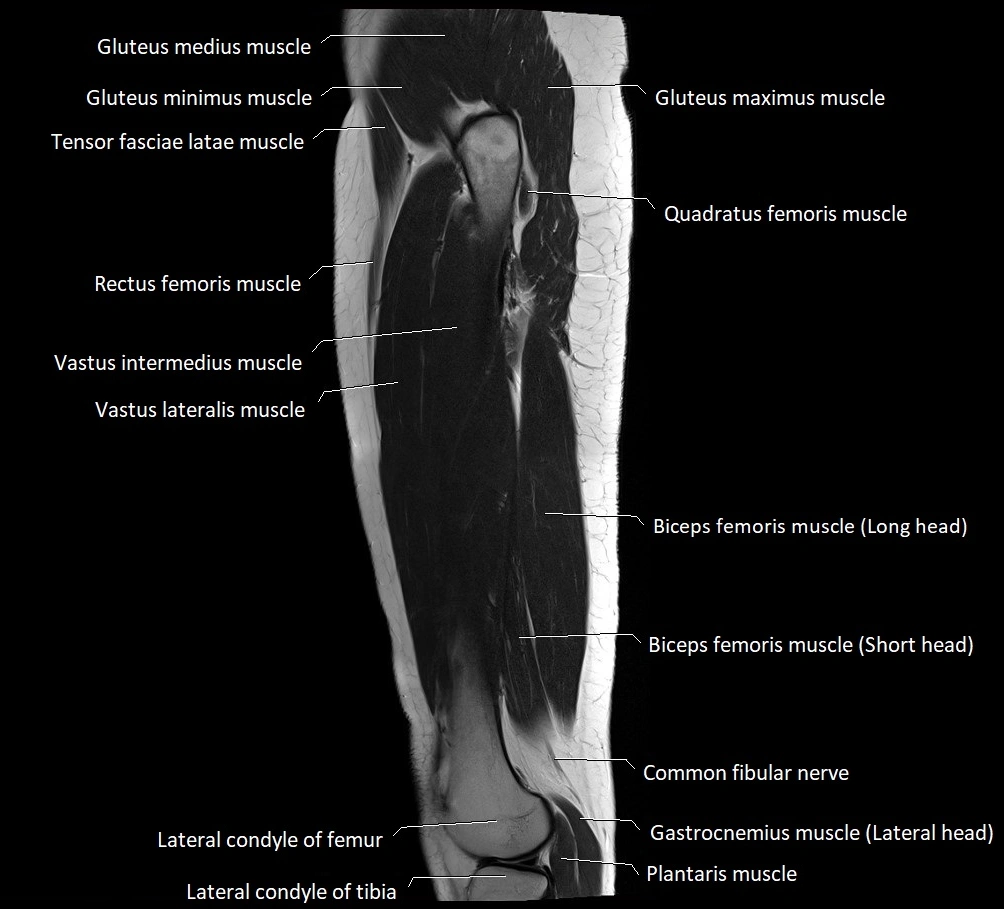

- Biceps femoris muscle (Long head)

- Biceps femoris muscle (Short head)

- Common fibular nerve

- Gastrocnemius muscle

- Gluteus maximus muscle

- Gluteus medius muscle

- Gluteus minimus muscle

- Gerdy’s tubercle

- Quadratus femoris muscle

- Rectus femoris muscle

- Vastus intermedius muscle

- Vastus lateralis muscle